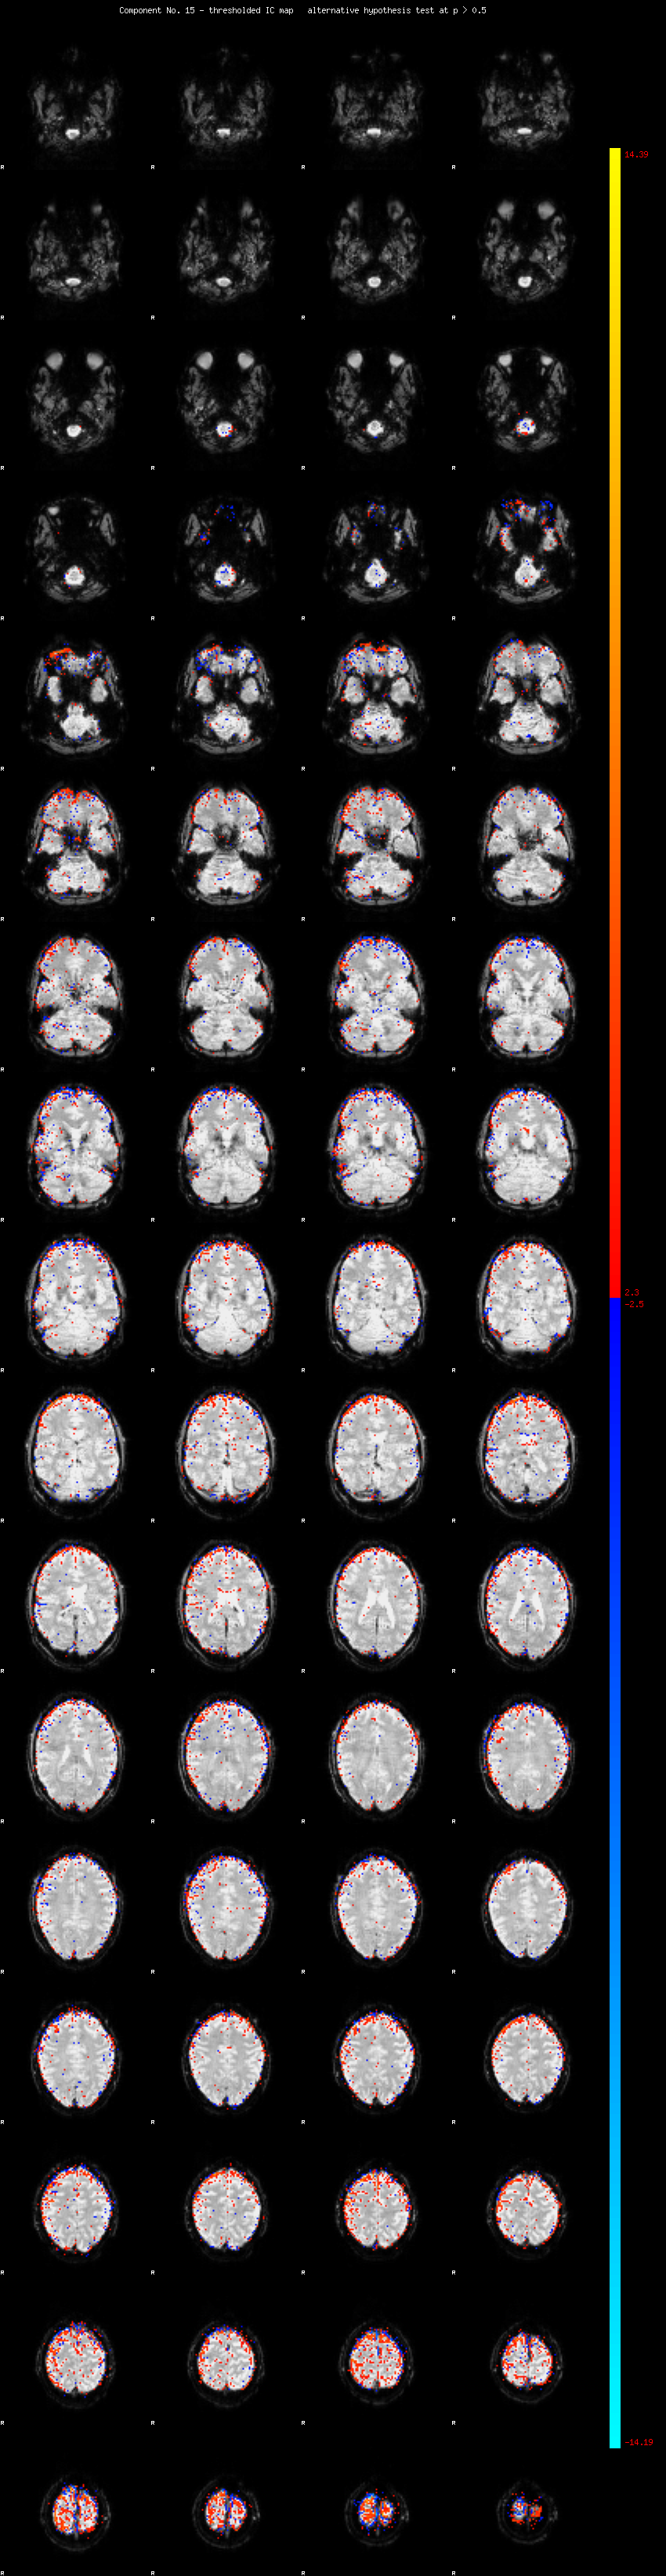

MELODIC Component 15

1.68 % of explained variance;     1.11 % of total variance